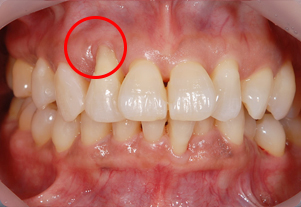

症例2(歯肉移植)

Before

After

- POINT

- 右上2番(赤丸の箇所)の歯茎が下がってしまった患者様です。

歯茎が薄く歯もしみてしまい歯磨きしにくいため、上あごから歯肉を移植しました。

厚みのある歯茎になり、しみる症状も改善されました。